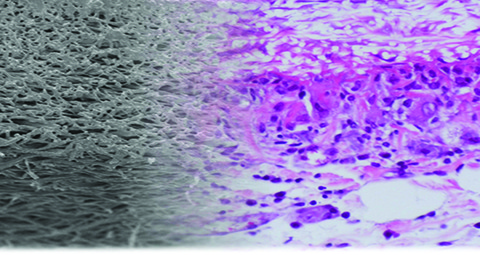

To create these artificial blood vessels, the team spun polymer solutions in an electrical field to form very fine threads which were arranged to simulate natural blood vessel walls. Then they used mass spectrometry to observe the interaction between the material – thermoplastic polyurethane – and blood cells in rats. The scientists found that the slightly porous nature of the polymer fabric allowed migration and colonisation of natural cells.

After six months, the team examined the inserted artificial blood vessels and discovered that the material showed no evidence of blood related problems. At the end of the process the artificial vessels turned into natural body tissue.

Professor Helga Bergmeister of the Medical University of Vienna said: “We did not find any aneurysms, thromboses or inflammation. Endogenous cells had colonised the vascular prostheses and turned the artificial constructs into natural body tissue.”